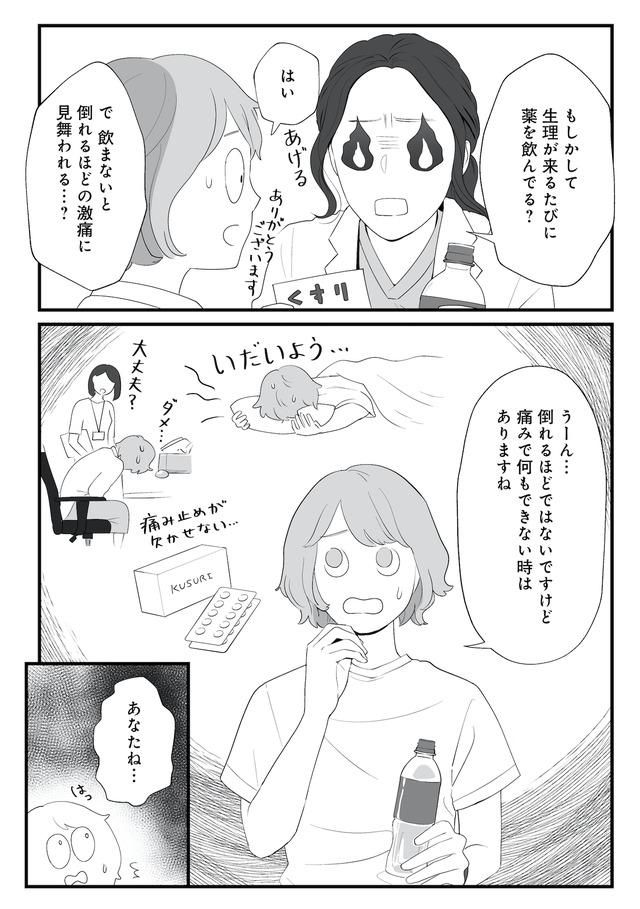

生理痛やPMSに苦しむあかり。通勤中、貧血で倒れて病院に運ばれたことをきっかけに、自分にあった生理用品や治療法を教えてもらうことに。

生理、吸水ショーツ、月経カップ、ミレーナ、ピル、卵子凍結、性のこと…

知ると知らないで大きく変わる! 自分のカラダとの向き合い方とは?

※本記事は、漫画・くゑ 、監修・高橋 怜奈 の書籍『産婦人科医に聞く わたしとカラダの選択肢』から一部抜粋・編集しました。